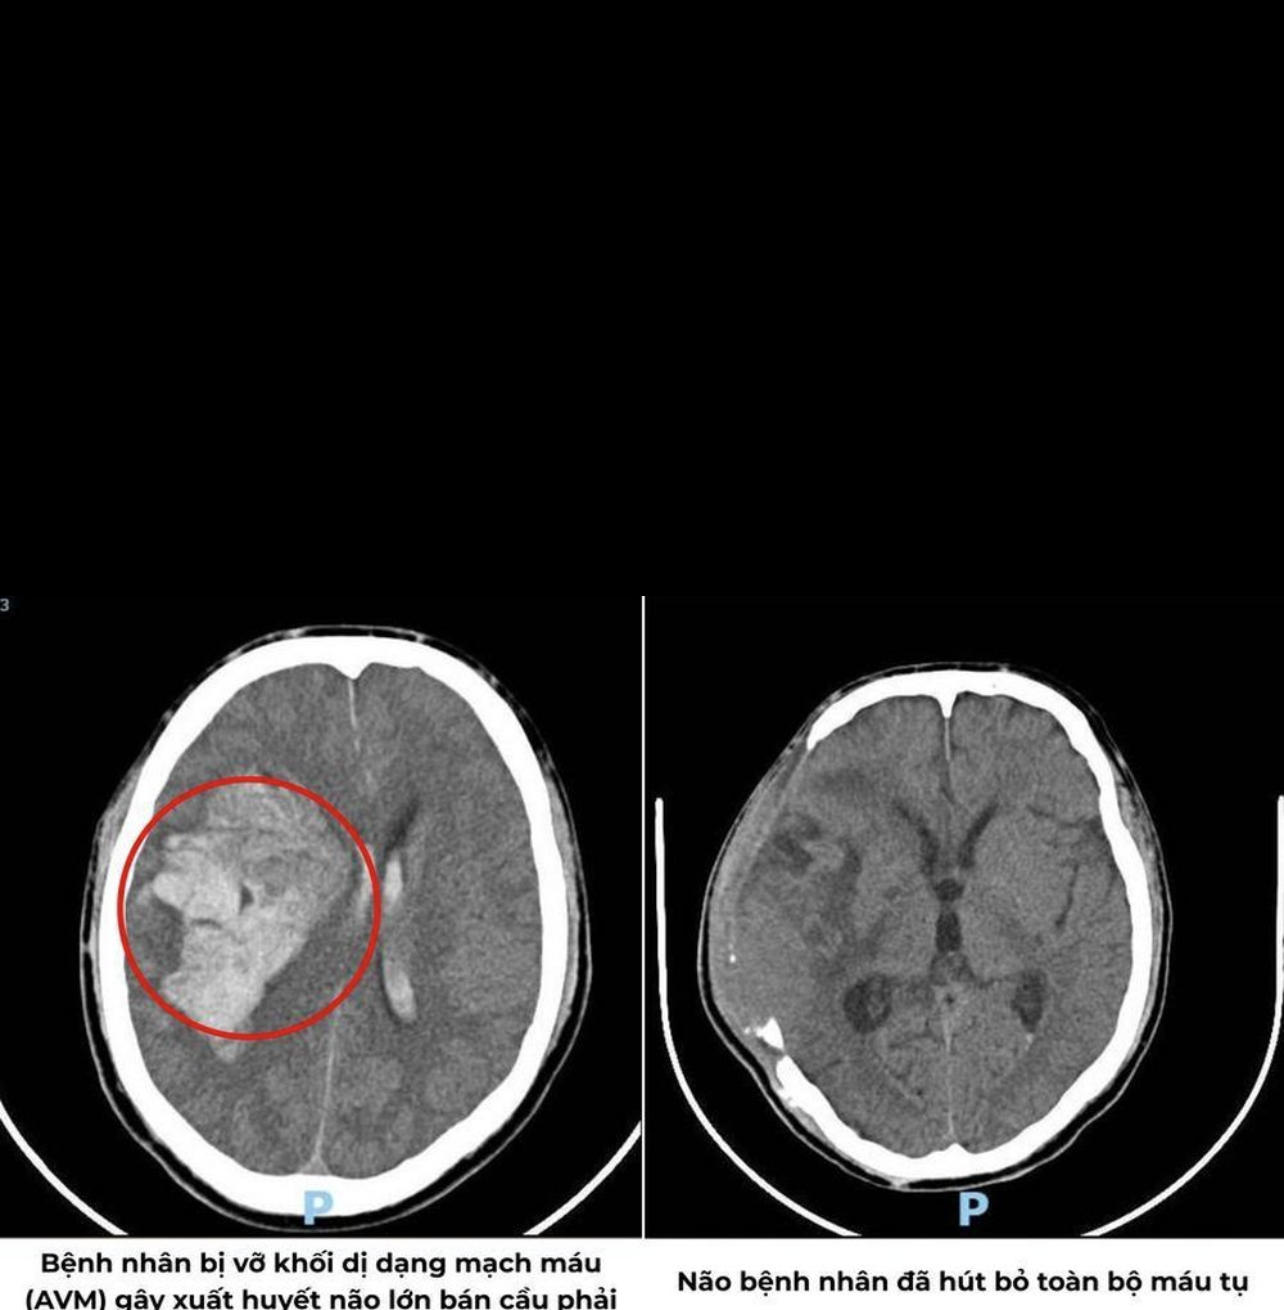

Kết quả chẩn đoán hình ảnh xác định bệnh nhân bị xuất huyết nội sọ lan tỏa nhiều vị trí, dị dạng thông động, tĩnh mạch nội sọ kích thước lớn và khối dị dạng gây chèn ép nhu mô não và đẩy lệch đường giữa.

Trong gần 3 giờ căng thẳng tại phòng mổ, các bác sĩ Khoa Ngoại Thần kinh mở sọ, kiểm soát điểm chảy máu, hút bỏ máu tụ trong não và giải phóng vùng chèn ép. Sau phẫu thuật, bệnh nhân được chuyển đến Khoa Hồi sức tích cực - Chống độc để theo dõi, chăm sóc và hồi sức.

Hình ảnh chụp trước và sau phẫu thuật. Ảnh: BVQT.

Lúc tình trạng ổn định, bệnh nhân được chỉ định chụp và can thiệp mạch số hóa xóa nền (DSA). Các bác sĩ tiến hành bơm keo tắc mạch chọn lọc qua đường động mạch cảnh trong. Ca can thiệp thành công với tỷ lệ nút mạch trên 95%, giúp loại bỏ gần như hoàn toàn nguy cơ tái xuất huyết.